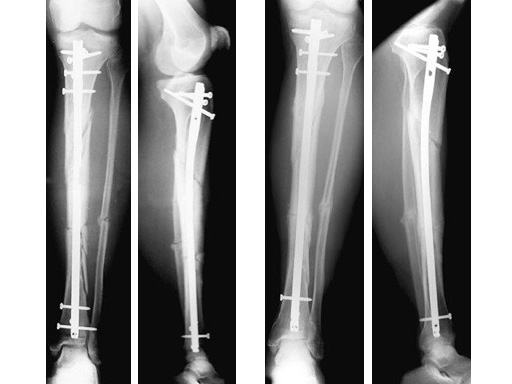

64-year-old woman with an open distal tibial fracture extending into the pilon treated with ETNS.